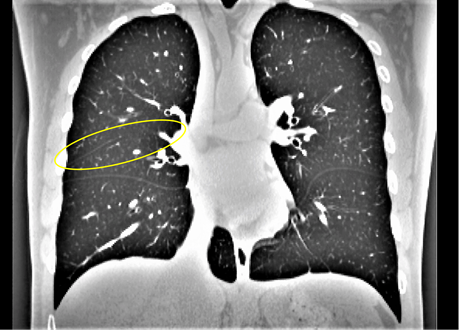

We argue that the sub-optimal paradigm of processing different abstractions within a single CNN pipeline can be remedied through the effective processing of information in a structured manner. Consequently, we devise strategies for disentangling the edge and texture information within a single training pipeline. Figure 2 illustrates how our proposed module, dubbed EG-CNN, can be paired with any existing CNN encoder-decoder to improve segmentation quality near intensity edges. We have applied our EG-CNN to the tasks of brain and liver tumor segmentation in medical images (Figure 3).

(1) Brain MR (2) Liver MR (3) Liver CT (4) Lung CT

Deep Active Lesion Segmentation

[45]: Lesion segmentation is an important problem in computer-assisted diagnosis that remains challenging due to the prevalence of low contrast, irregular boundaries that are unamenable to shape priors. We introduce Deep Active Lesion Segmentation (DALS), a fully automated segmentation framework that leverages the powerful nonlinear feature extraction abilities of FCNs and the precise boundary delineation abilities of ACMs. Our DALS framework benefits from an improved level-set ACM formulation with a per-pixel-parameterized energy functional and a novel multiscale encoder-decoder CNN that learns an initialization probability map along with parameter maps for the ACM. We evaluate our lesion segmentation model on a new Multiorgan Lesion Segmentation (MLS) dataset that contains images of various organs, including brain, liver, and lung, across different imaging modalities—MR and CT. Our results demonstrate favorable performance compared to competing methods, especially for small training datasets. -